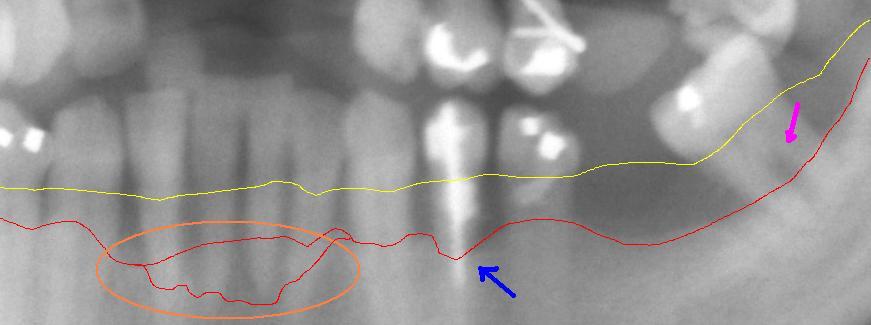

치은연상 치태는 잇몸 위에 형성되는 치태로, 칫솔질 후 가장 먼저 형성된다. 이는 일반적으로 치아 사이, 치아의 홈과 틈새, 잇몸선을 따라 형성된다. 주로 호기성 세균으로 구성되어 있으며, 이는 이러한 세균이 생존하기 위해 산소가 필요하다는 것을 의미한다. 치태가 치아에 오랫동안 남아있으면, 혐기성 세균이 이 치태에서 자라기 시작한다.[5]

치은연하 치태는 잇몸 아래에 위치한 치태이다. 잇몸 위에서 아래로 세균이 성장하면서 치은연상 치태가 형성된 후에 발생한다. 이 치태는 대부분 혐기성 세균으로 구성되어 있으며, 이는 이 세균이 산소가 없을 경우에만 생존한다는 것을 의미한다. 이 치태가 잇몸 아래의 포켓에 부착되면 입 안의 산소에 노출되지 않으므로 제거하지 않으면 번성하게 된다.[10]

치태는 잇몸을 기준으로 잇몸 위에 형성되는 치은연상 치태와 잇몸 아래에 형성되는 치은연하 치태로 나눌 수 있다. 치은연상 치태는 칫솔질 후 가장 먼저 형성되며, 주로 치아 사이, 치아의 홈과 틈새, 잇몸선을 따라 형성된다. 주로 호기성 세균으로 구성되어 있으며, 치태가 오랫동안 남아있으면 혐기성 세균이 자라기 시작한다.[5] 치은연하 치태는 잇몸 아래에 위치하며, 대부분 혐기성 세균으로 구성되어 있다.[10]

치태는 잇몸에 염증을 일으키는 치은염을 유발한다.[21] 치은염은 잇몸이 붉게 부어오르고, 칫솔질이나 치실 사용 시 피가 나는 증상을 보인다.[22] 치태로 인한 치은염은 치태를 제거하면 회복될 수 있지만, 오랫동안 방치하면 염증이 잇몸 주변 조직까지 퍼져 치주염으로 진행될 수 있다.[23]

치주염은 잇몸 감염으로 인해 턱뼈(치조골)가 파괴되는 질환이다. 치주염은 치은염이 발생한 후에 나타나지만, 모든 치은염 환자가 치주염으로 진행되는 것은 아니다.[3][24] 치주염의 주요 원인은 치태 축적이며, 치태 속 세균은 뼈를 공격하여 파괴하는 효소를 방출한다. 동시에 뼈 속의 파골세포가 추가 감염을 막기 위해 뼈를 분해하여 치아 손실을 초래한다. 치주염은 칫솔질 및 치아 사이 세척과 같은 철저한 구강 위생 관리와 치과 전문의의 치석 제거술을 통해 치료할 수 있다.[25]